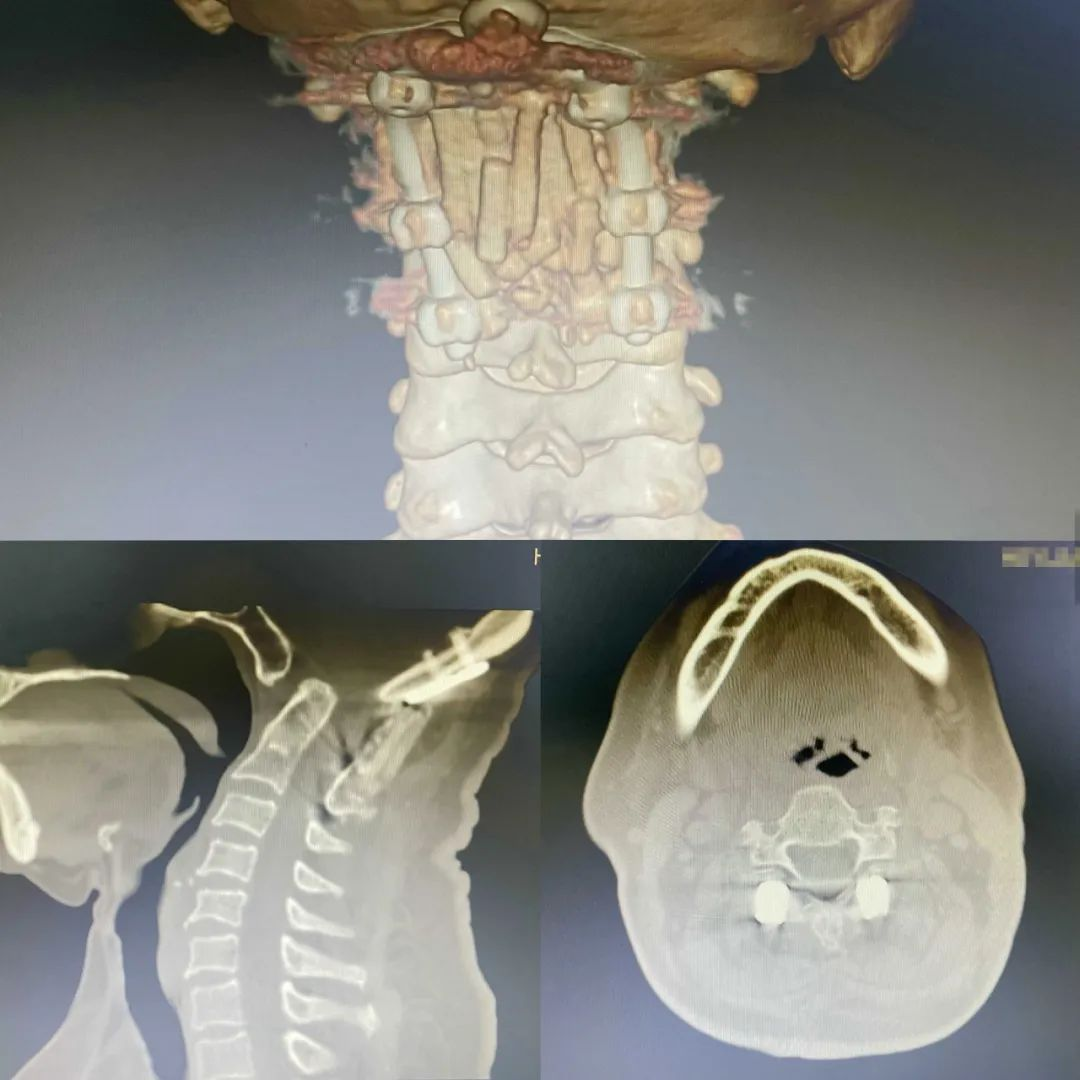

▲术后复查颈椎CT

完成手术2天后患者开心地说:“当时医生告诉我得了这么个病,听都没听说过,我都以为这辈子完了,没想到医生技术这么好,这才第2天我就能下地走路了。”术后患者头晕头痛症状减轻,2天拔除引流管下床活动,四肢活动较前灵活有力,肢体麻木较前减轻,不久之后顺利康复出院。